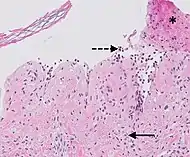

| Urticaria, lymphocyte predominant | Perivascular location. Mast cells are relatively sparse, potentially demonstrated with special stains, preferably tryptase stain. Extravasated erythrocytes are present in about 50% of the cases. No vasculitis.[14] | Dermal edema [solid arrows in (A,B)] and a sparse superficial predominantly perivascular and interstitial infiltrate of lymphocytes and eosinophils without signs of vasculitis (dashed arrow).[15] |

![]() |